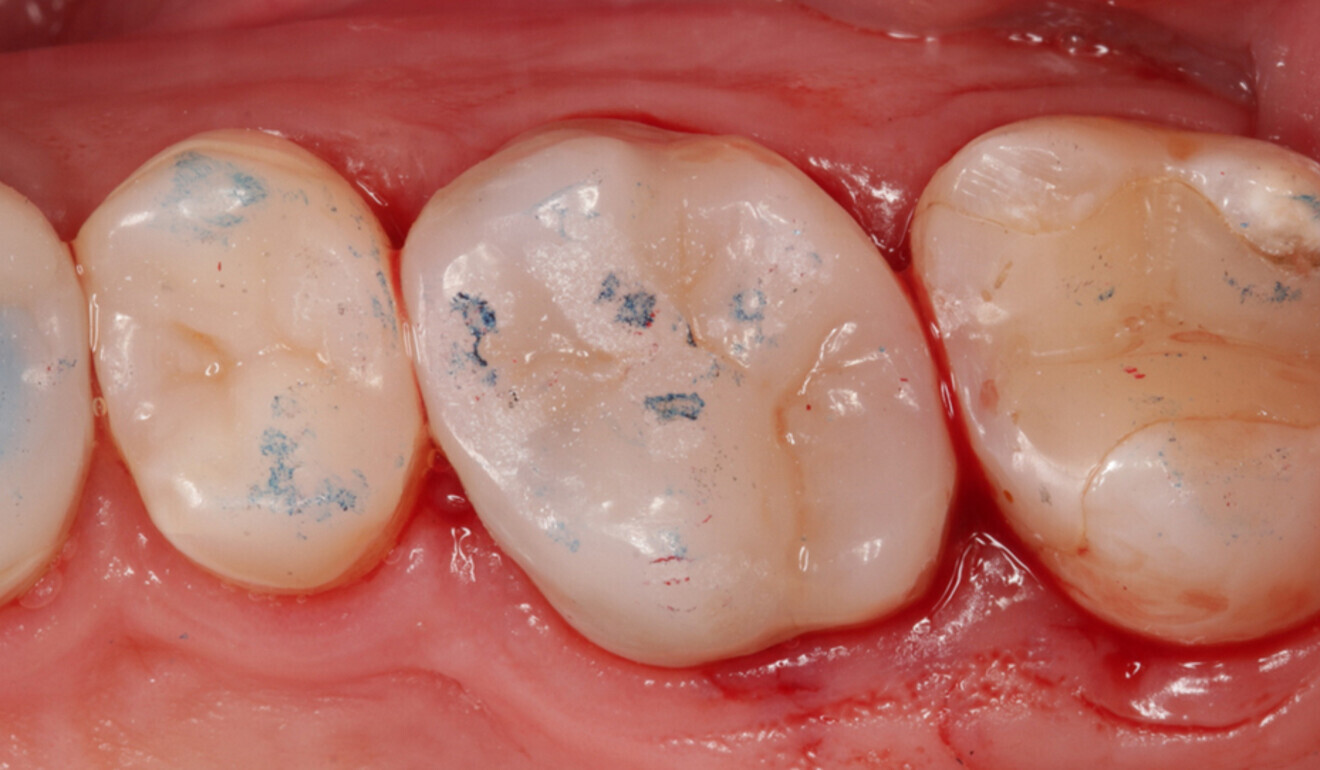

After removal of the dental dam, the occlusal contact points of the direct overlay were adjusted (Figs. 18 & 19). Every spot touched by the bur was subsequently repolished according to the previously described protocol (Figs. 20 & 21).

Fig. 18: Occlusal adjustment. Contact points recorded with articulating paper (100 μm). (Image: Kuraray Noritake Dental)

Fig. 19: Occlusal adjustment. Contact points recorded with articulating paper (100 μm) and articulating foil (16 μm). (Image: Kuraray Noritake Dental)